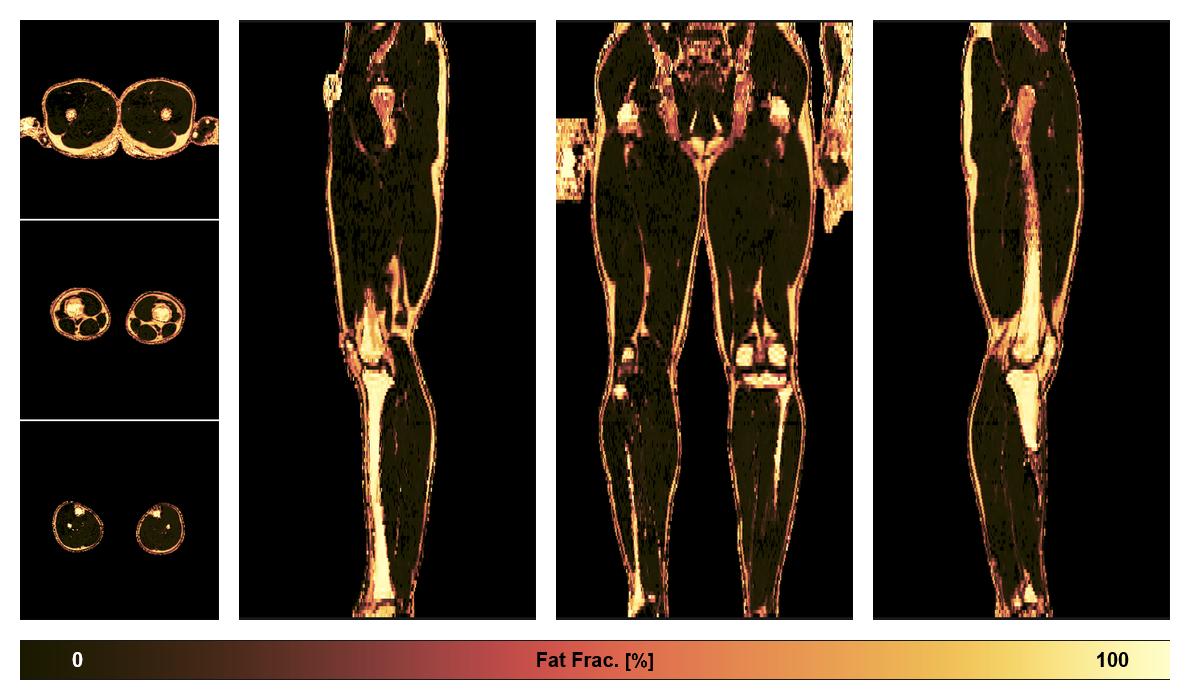

• Fat fraction

The fat fraction of the lower extremity obtained from the dixon reconstruction for muscle water fat quantification.